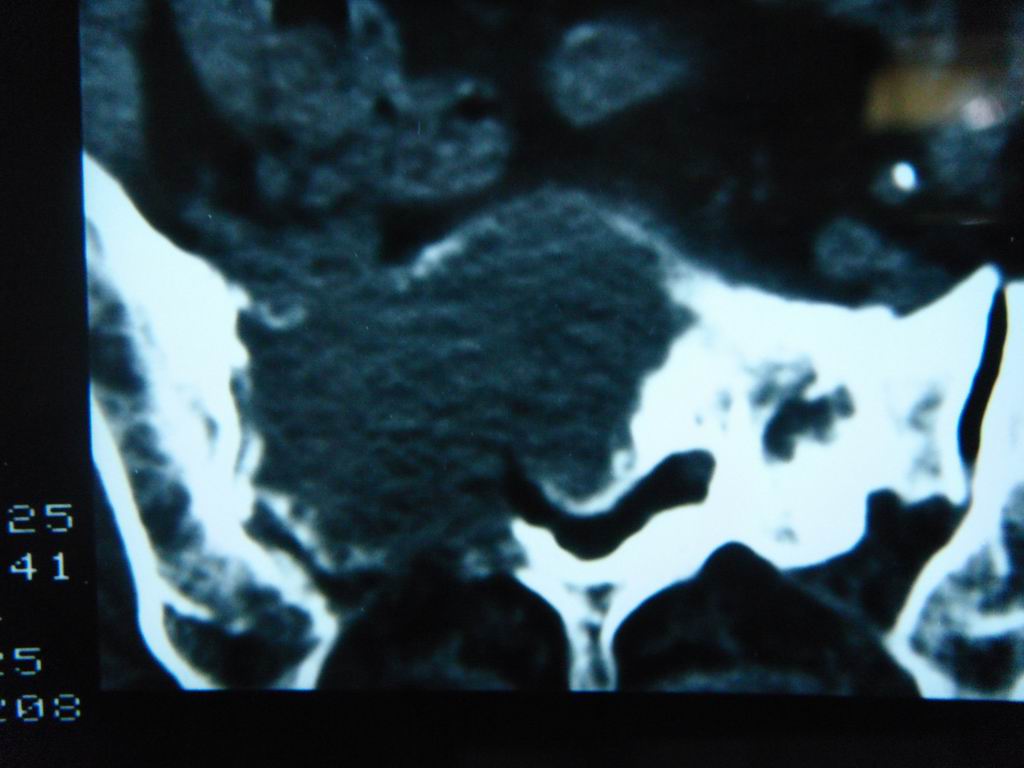

标题: CT21430:女性65岁 乳腺癌术后3年 [打印本页]

标题: CT21430:女性65岁 乳腺癌术后3年

结合病史,考虑骶骨转移瘤,但软组织肿块未突破骨壳,骨巨细胞瘤不能完全排除,骨髓瘤及脊索瘤不考虑。

结合病史,考虑骶骨转移瘤。

结合病史,考虑骶骨转移瘤。其它椎体,如腰5是否有问题呢?

个人感觉骨巨细胞瘤可能性大些。